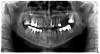

Igor V. Опубликовано 20 июня, 2011 Поделиться Опубликовано 20 июня, 2011 Прошу проанализировать снимок и предложить возможные варианты решения проблемы.Сейчас мне 33 года, плотно начал решать проблемы с зубами 8 лет назад. В то время были перелечены все каналы, поставлены 4 моста и несколько коронок.8 месяцев назад неожиданно появился флюс, при этом ничего не болело и не беспокоило, проблема была локализована на верхней челюсти слева.После нескольких консультаций было принято решение мост (2.4, 2.5, 0, 0, 2.8) распилить, 2.5. удалить.Спустя 3 недели после удаления была проведена операция по подсадке в область 2.6, 2,7 "костной ткани".Имплантация была запланирована на май. Со сроками немного затянул, а в начале июня появился свищ в области 2.7. Хирург сказал, что это не помешает нам имплантироваться, так как "мы все накроем антибиотиками" Такой ответ меня не устроил и я пошел к другому врачу на консультацию.Его мнение было таковым, что на фоне проблем с костной тканью в области подсадки, а также множественных кистогранулем ни о какой имплантации не может идти речи, требуется полная санация полости рта, с разборкой мостов, извлечением вкладок, перелечиванием каналов. Причем без гарантии, что на место разобранных мостов можно будет поставить новые мосты, так как вкладки слишком большие и аккуратно их снять, не разрушив окончательно корни, вряд ли получится, также никто не может поручиться за то, что удастся полноценно перелечить каналы.Я в полном замешательстве и прошу совета. Ссылка на комментарий

Bier Опубликовано 21 июня, 2011 Поделиться Опубликовано 21 июня, 2011 46,37 - так однозначно удалять. спасти их не получится имхо. Ссылка на комментарий